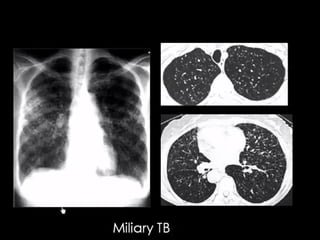

Miliary TB

Random distribution

Small random nodules are

seen in:

๏ฌ Hematogenous metastases

๏ฌ Miliary tuberculosis

๏ฌ Miliary fungal infections

๏ฌ Sarcoidosis may mimic this

pattern, when very extensive

๏ฌ Langerhans cell histiocytosis

(early nodular stage)